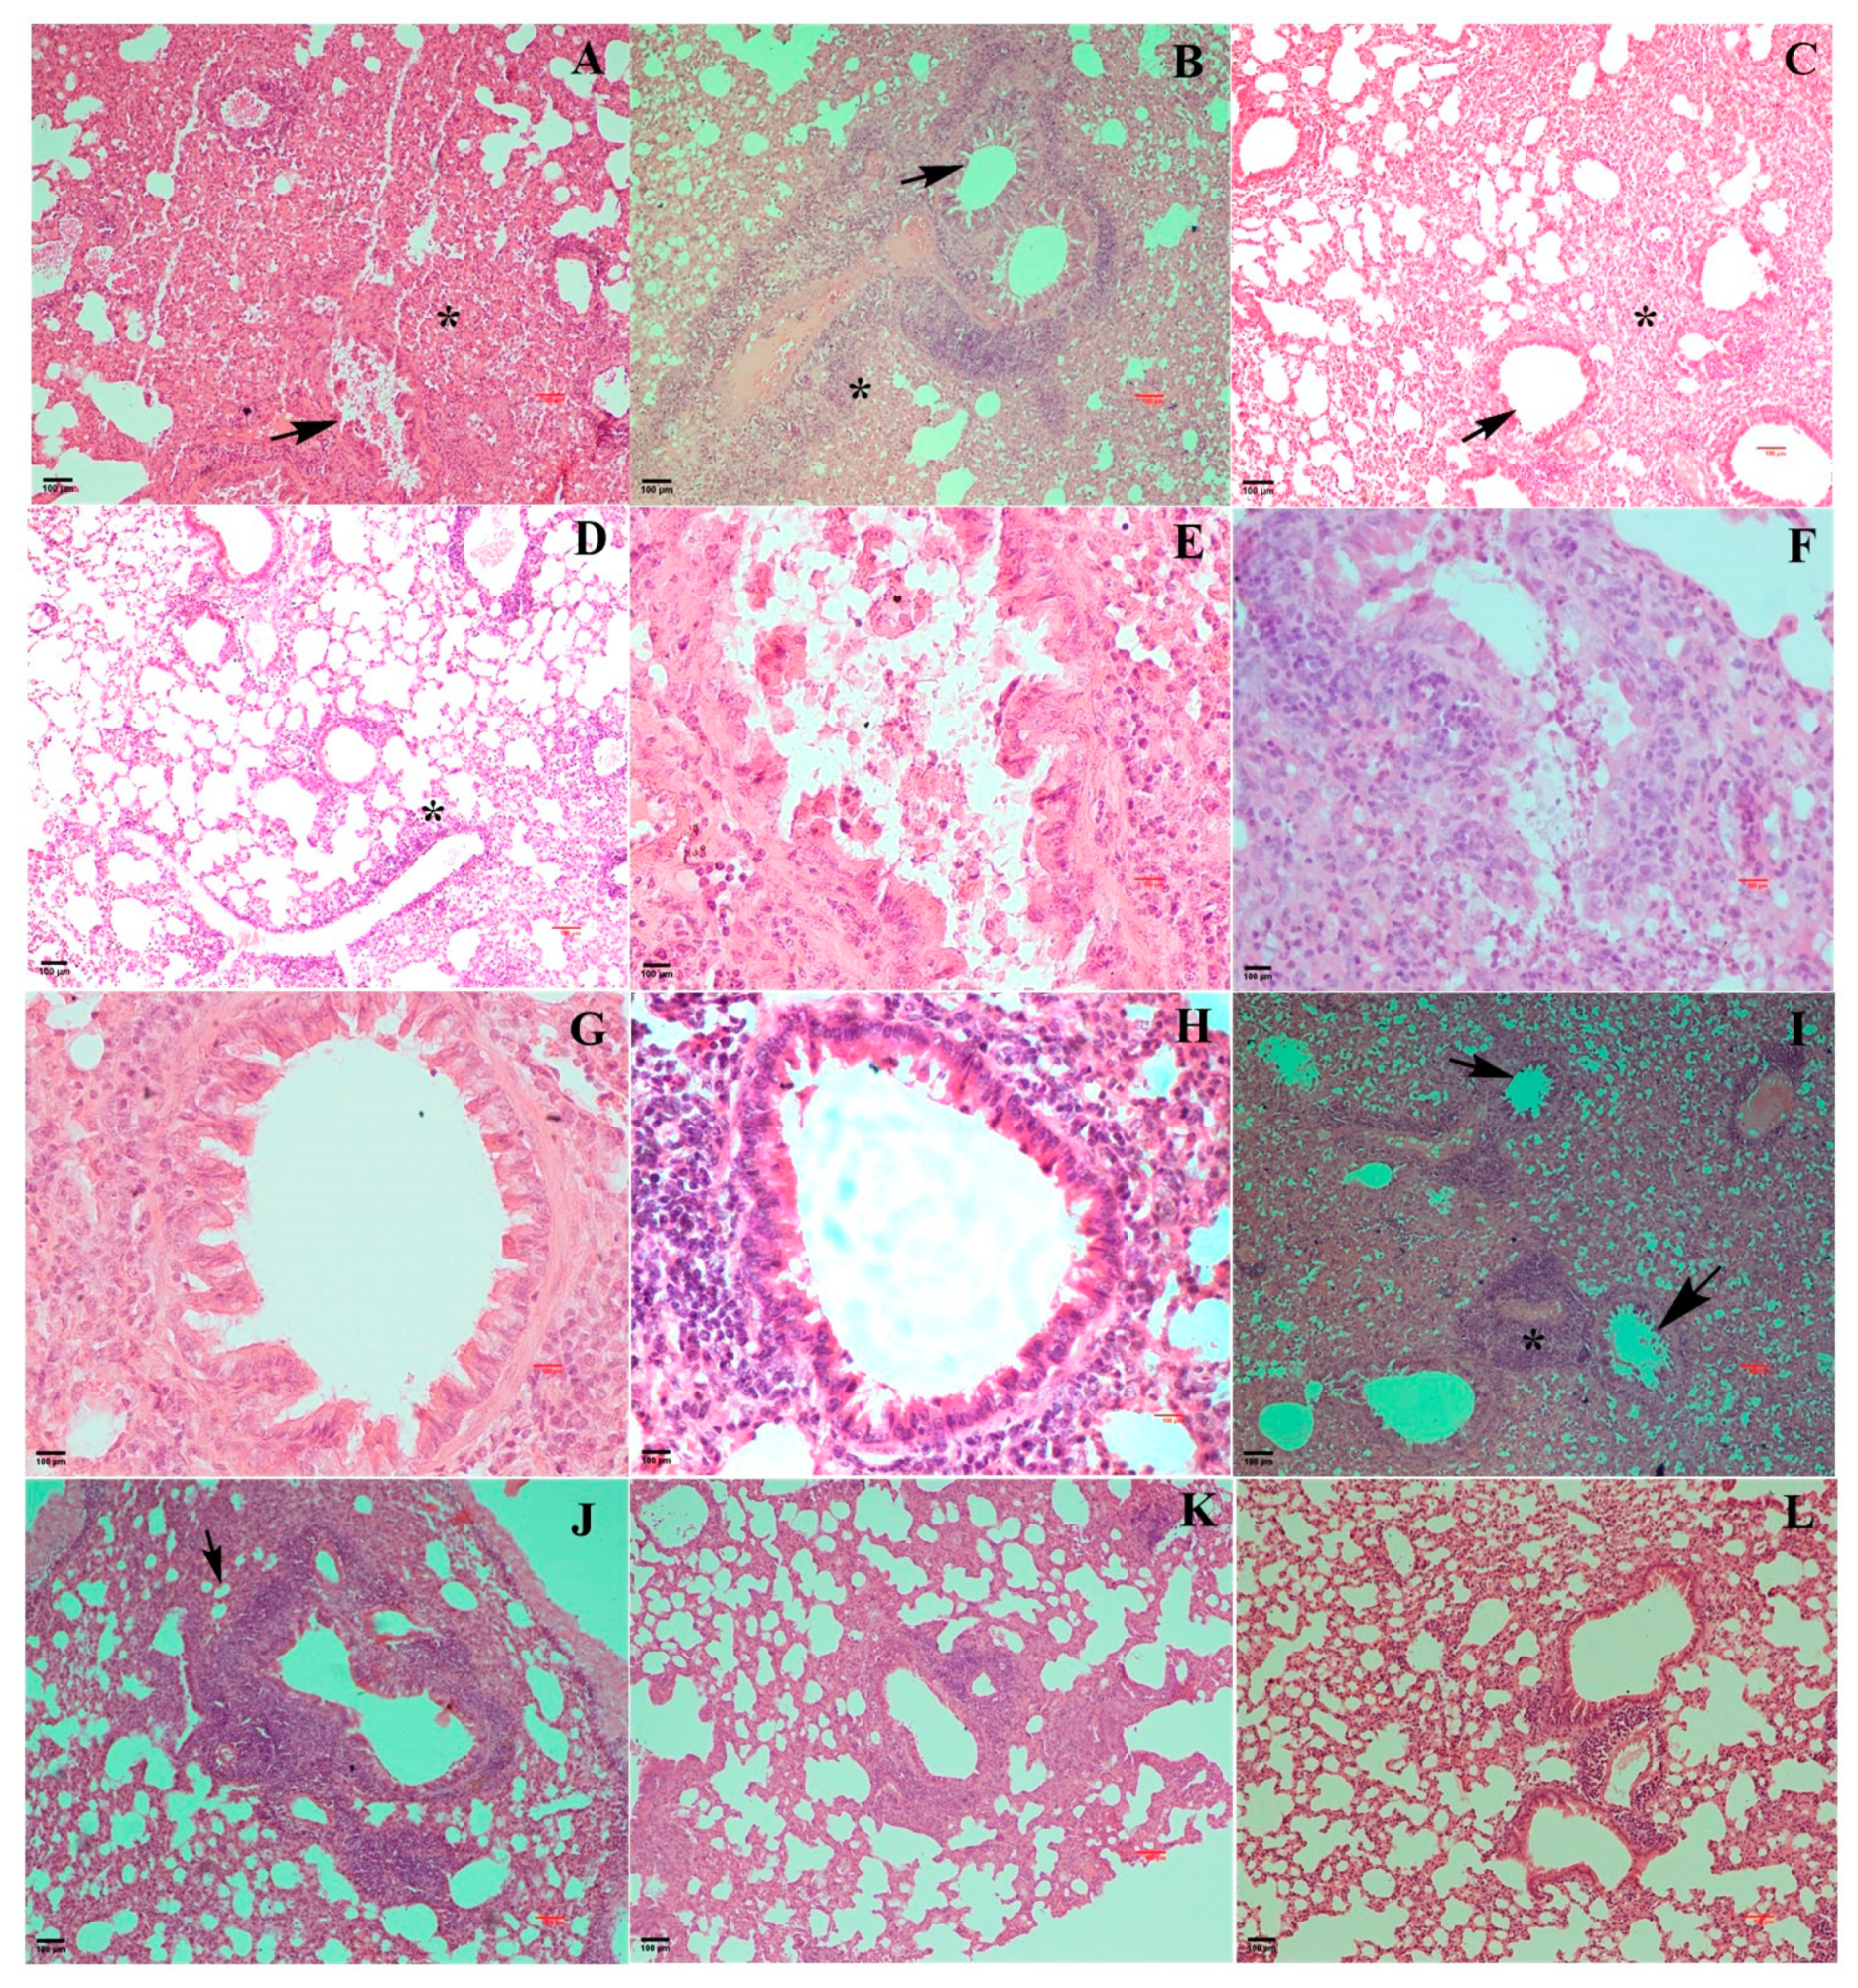

3.4. Pathological Changes Exhibited by EHV1 Mutants Vis-à-Vis Wt Post-Challenge